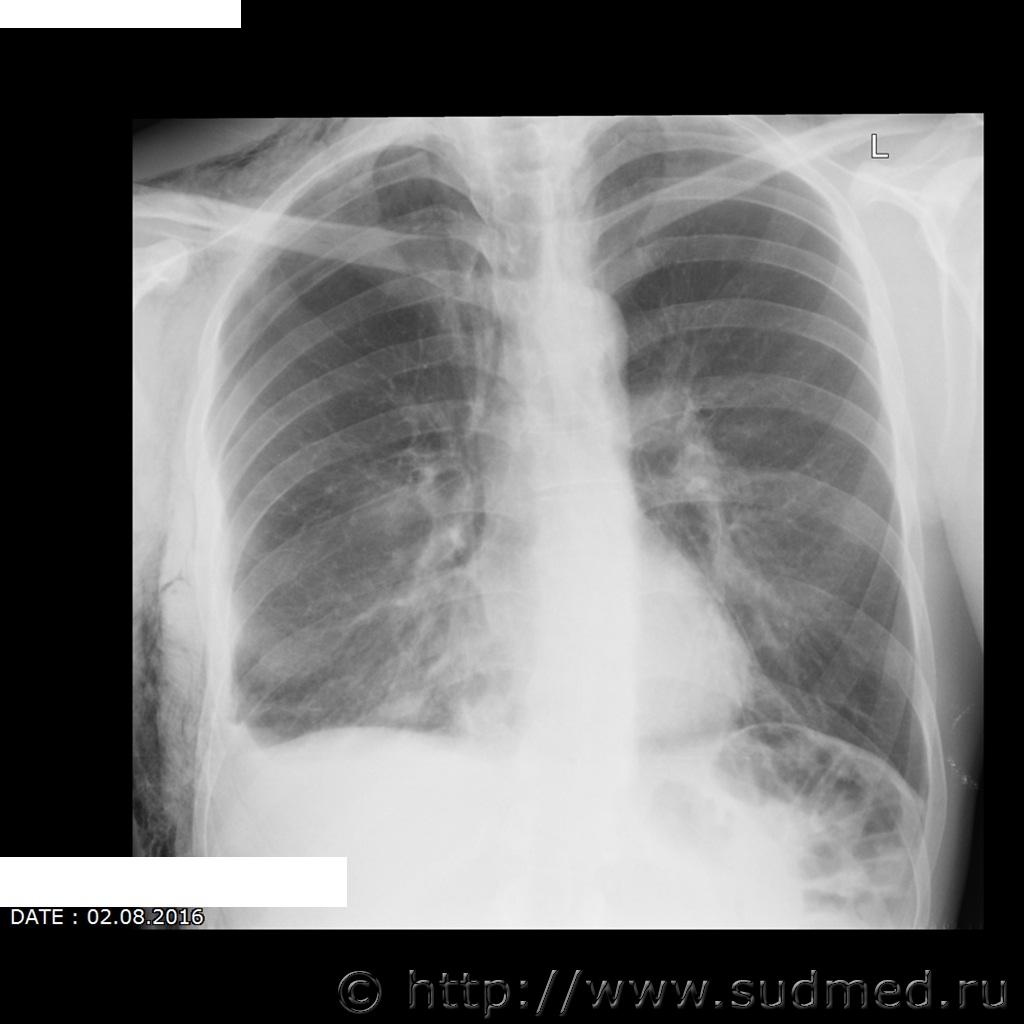

Травматический пневмоторакс справа, подкожная эмфизема, перелом (5, 7, 8 как минимум) правых ребер. Удары (удар) в правую боковую поверхность.

Согласен с коллегой: пневмоторакс справа (воздух в правой плевральной полости), обширная подкожная и межмышечная эмфизема правой половины груди (воздух в мягких тканях грудной стенки), вероятно, эмфизема распространяется и на шею. Переломы 5, 6, 7,8 ребер по передней подмышечной линии.

1. Представляется ли возможным объективно установить разрыв лёгкого по имеющимся рентгенологическим данным?

2. Возможно ли образование таких переломов по одной анатомической линии при обстоятельствах описанных свидетелем?

3. Имеются ли признаки повторной травматизации для определения количества нанесённых ударов (удара) в область перелома?

4. Возможно ли определить давность перелома ребер? Какой минимальный срок образования (по снимку от 30.07.2016 г.)

5. От какого количества травматических воздействий и от какого предмета мог образоваться этот перелом?

1. Пневмоторакс при тупой травме грудной клетки возникает вследствие разрыва легкого отломками ребер. Так что считайте разрыв объективно (пусть косвенно) установленным.

2. Возможно.

3. На сканах этого не различить, да и изучение нативных р-грамм в этом вопросе малоинформативно (не знаю о рентгенологических признаках пт).

4. На сканах нет признаков регенерации. Минимальный срок - "только что".

5. Минимум 1 удар тупым твердым объектом.